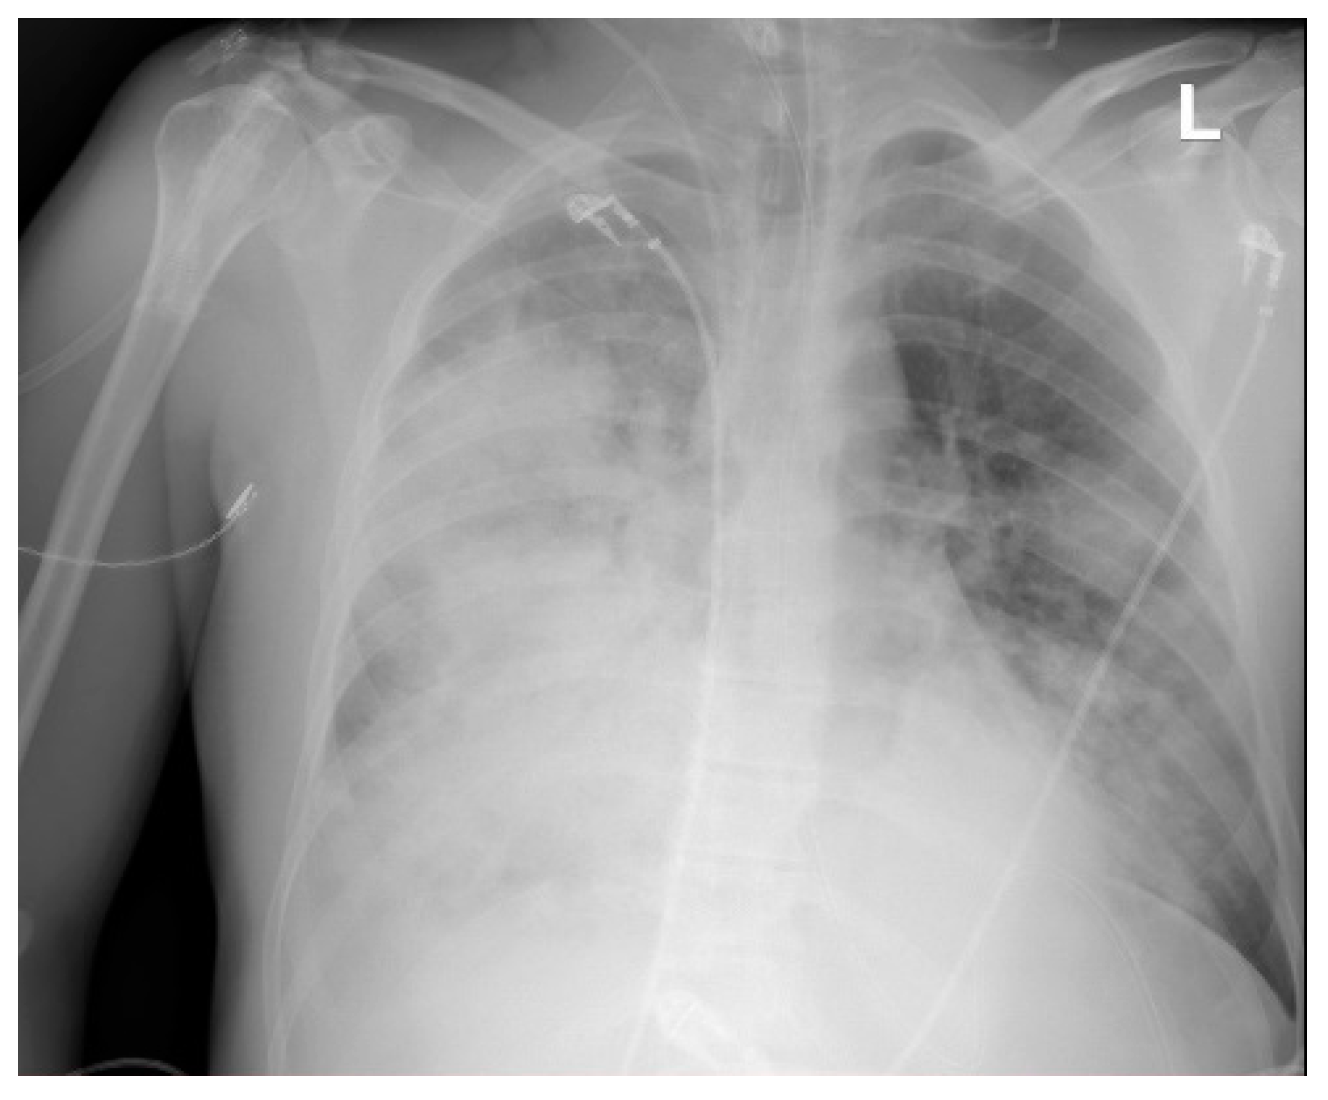

| 11 | 35/M | Pneumonia ARDS | none | Rhinovirus/Enterovirus (PN+) c | 21 | 15 | yes | 19 days | Transferred to the transplant center |

| 11 | Septex ECMO c | no | sputum + (PN+) d | Ertapenem Linezolid | Ertapenem Linezolid Penicillin |